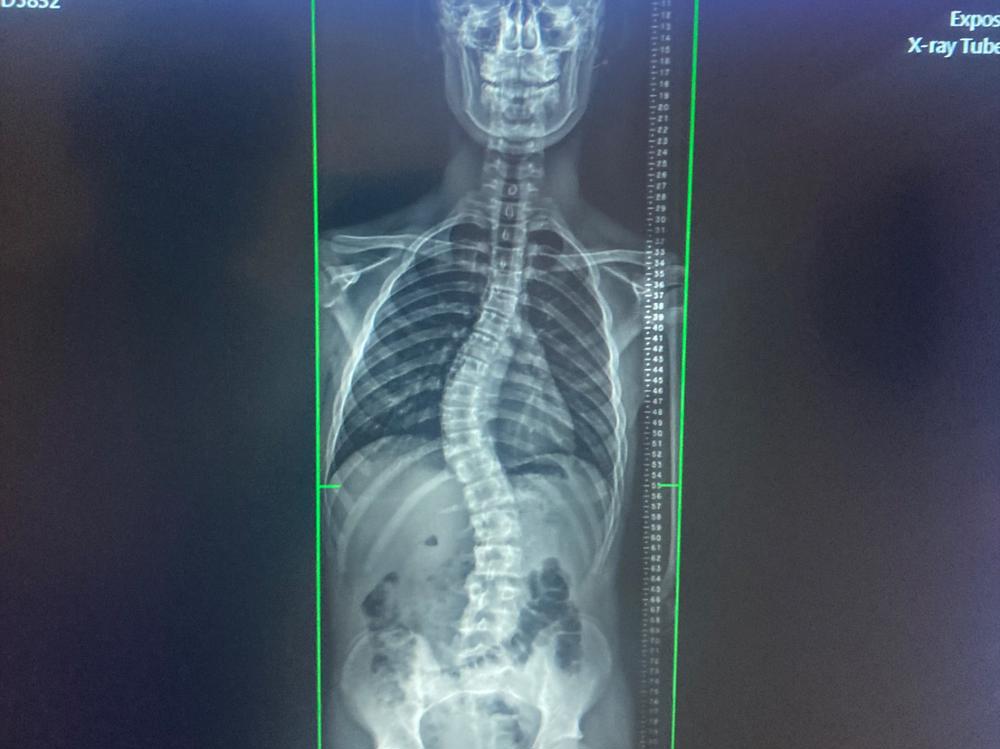

Logan’s Scoliosis Journey

Logan is our 15 year old, cheeky, athletic, basketball mad, son.

He was first diagnosed with Scoliosis in 2021 with a 36.2 degree curve. 8 months later, it’s now a 42.7 degree curve of his spine (which is a fast progression).

In NZ, surgery is the only solution which has been offered by the hospital when he gets to a 50degree curve. The surgery has a risk of paralysis so it’s not an option for our son.

The Scoliosis Care Center in California, provides a non surgical treatment plan to reduce Logan’s curve and hold it long term. However, this is not a funded treatment so we are raising funds with the help of kind and caring Kiwis to help us pay for the next two to three years treatment for Logan and his scoliosis. You can read more here: www.Facebook.com/LSJ06